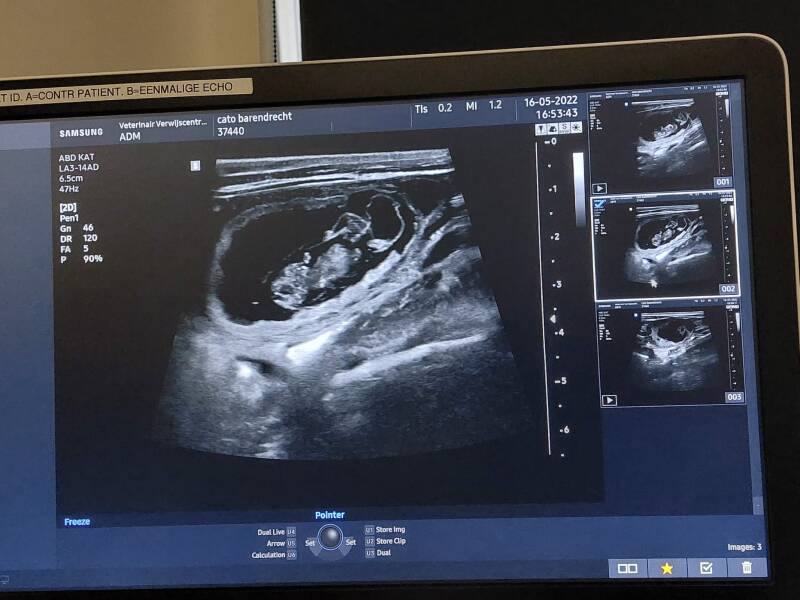

En jawel...kleine pups gesignaleerd!

Maandag 16 mei is eigenaresse Nicky met Cato naar de dierenarts geweest om te checken of er iets leuks gaande is daar binnen in het buikje. Nou had Nicky al het positieve vermoeden aangezien Cato veel rustiger is en er ook andere eetgewoonten op na houdt. Liever verse kip dan de doorsnee brokjes... Maar zeker weten doe je het natuurlijk nooit. Gelukkig zag de dierenarts al snel leven in de brouwerij. Niet een buik vol, maar goed, pups kunnen zich aardig verstoppen dus hoeveel er aan het groeien zijn, blijft nog even spannend. Wel zijn we weer een stapje verder in de planning. Alle mensen die zich tot nu toe hebben gemeld krijgen een mail met meer informatie. Mocht je die niet hebben ontvangen, laat het dan even weten.